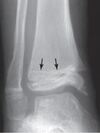

Linha de parada de crescimento?

Quando ocorre parada de crescimento observa-se uma linha esclerótica na região que parou de crescer → linha de parada de crescimento de **Harris**: confirmação da presença de verdadeira parada do crescimento